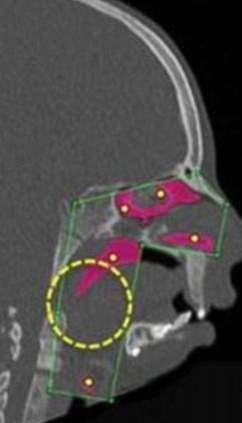

▼他们决定旋转汉娜部分的骨骼,让她的气管能够因此畅通连接,经历一系列的手术并休养后,汉娜终于在近日接受了最重要的气管重建手术,也来到她目标的最后一步。